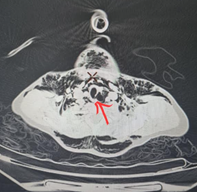

CT scanner revealed a tracheal rupture of the posterior edge of the cervicothoracic trachea at the level of C7-T1, approximately 4 mm in length, complicated by a pneumomediastinum without involvement of the mediastinal organs, as well as significant subcutaneous emphysema. low-volume both sides pneumothorax (Figure 3). There was no pulmonary parenchymal abnormality, nor at the level of the cervical spine or rib cage.

Figure 2: CT image showing tracheal rupture of the posterior edge of the cervicothoracic trachea at the level of C7-T1, approximately 4 mm in length, complicated by a pneumomediastinum.